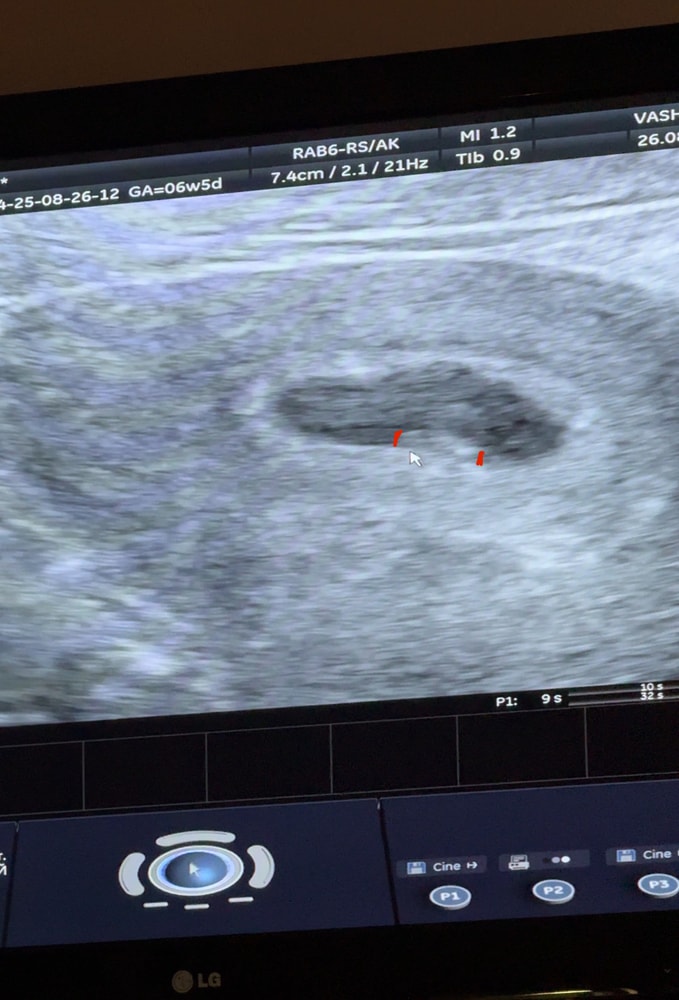

Нас увидели (УЗИ 6 недель)🥹

УЗИ, КТГ, доплерСегодня 6+5 (по М), но овуляция была поздняя И каково было мое удивление, что даже на узи через живот нас очень хорошо видно уже, КТР 5мм, и даже слышно сердечко❣️

Срок доктор написала 6+1 (согласно КТР)

P.S. Снимала на видео, поэтому поймать скриншот было сложно, где хорошо видно)

UPD: чсс 154 уд/мин☺️